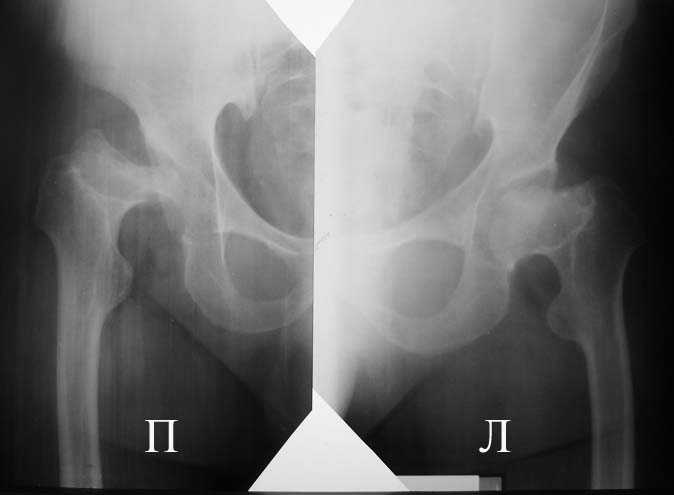

Прямая проекция т/б суставов

Алексей, судя по снимкам, правый тазобедренный сустав нуждается в замене. Думаю, что получится поставить протез без дополнительных конструкций во впадину и особых ножек. Важным является диаметр канала. Надо по шаблонам оценить размер. Самые маленькие из известных мне ножек в России предсталены у De Puy (бесцементная 6), и новинка от BIOMET бесцементная диспластическая ножка.

Алексей, качество Р-грамм не очень хорошее, канал виден только в одной плоскости (по-моему аксиальной), размеры кости не понятны. Думаю что можно подрыться без к/пластики, но головка то есть всегда. Канал не виден, ничего не могу сказать. Но наверно можно Аллоклассик с подстраховкой Вагнером.

По одной рентгенограмме тазобедренного сустава сложно ответить на вопрос о возможности протезировния (коленных особенно).

Если есть возможность прислать снимки таза и прямую проекцию тазобедренного сустава с бедром, то можно будет обсудить и вероятность и перспективы.